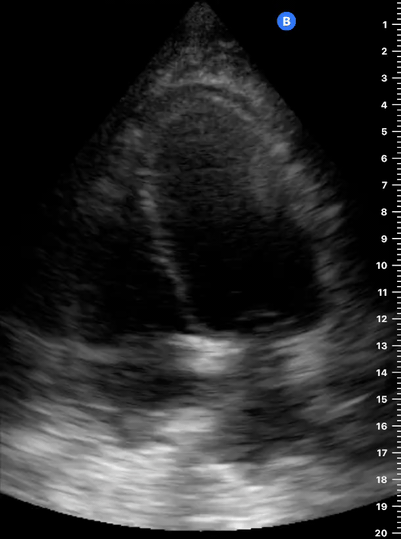

Exit: is there acute aortic root pathology?

Thoracic Aortic dissection is a time-dependent and deadly pathology that can occur silently or be masked by a variety of clinical presentations. While angio-CT remains the gold standard for diagnosis, US may be performed quicker and at the bedside. In the visible portion of the aortic root, the US findings can include intimal flap, aortic valve insufficiency, retrograde aortic flow, or rupture into the pericardium with pericardial effusion and tamponade. Alternatively, dilation of the aortic root is characteristic of a thoracic aortic aneurysm.

Importantly, remember that thoracic aortic dilation or intimal flap may occur distal to the aortic root, where an US scan is usually blind. Hence, the absence of dilation or flap does not rule out aortic disease.

THE VIEWS

The PLAX view is best for exploring the aortic root. If performed by an experienced operator, aortic root measurements in this window correlate well with angio-CT measurements.

The Aortic root size varies with age and gender and should be measured at its widest point, perpendicular to its long axis. In general, a root > 4 cm should be considered borderline and enough to warrant a formal study.

Alternatively, the aortic root size can be estimated by the rule of thirds, where in the PLAx view the size of the RV, AoR, and LA should be roughly 1:1:1.

AORTIC DISSECTION

In both of these views, US may detect an intimal flap seen as a hyperechoic linear structure within the aortic lumen that moves with each heartbeat. The visualization of a flap carries a high specificity and should prompt immediate consultation with cardiothoracic surgery; however, ultrasound sensitivity for intimal flap is significantly low, and its absence does not rule out aortic dissection.